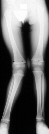

This 2 year and 9 month old male presented for evaluation

of a worsening valgus deformity of his right knee. Thirteen months

ago, his mother states the patient complained of some right leg

pain and a limp, unassociated with recognized trauma. The pain

and limp resolved over a number of weeks. Mom has noticed a progressive

cosmetic deformity of the leg without any complaints of pain or

functional limitation in running or walking. At the time of the

initial injury, the patient was examined by his doctor but there

was no history of injury and the problem was not considered to

be significant; therefore, no x-rays were performed to document

the possibility of a fracture. On physical examination moderate

to severe genu valgum of 25 degrees of the right knee and 5 degrees

of genu valgum of the left knee was noted. The right knee had

full, painless range of motion without ligamentous instability.

The left iliac crest was higher than the right. There was no significant

rotational deformity noted at the hip, knee or ankle. On gait

examination, patient was able to walk and run without tripping

or displaying a functional deficit. Standing AP films of the bilateral

lower extremities revealed a tibial femoral angle of 17 degrees

of the right knee.